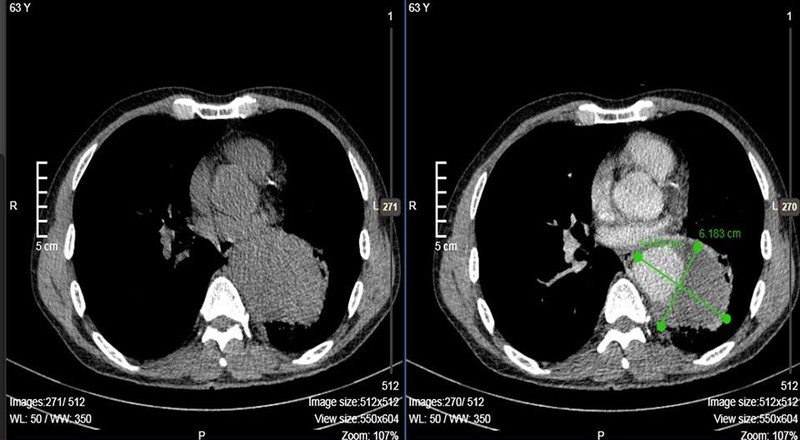

Ảnh chụp CT cho thấy động mạch của anh Q. bị phình